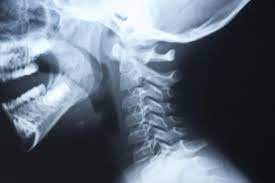

What Does Throat Cancer Look Like On An X Ray : Esophageal Cancer Diagnosis Imaging Tests Moffitt - For instance, voice changes may be a sign of laryngeal (voice box) cancer, but they would rarely indicate cancer of the pharynx.. It shows a view from ear to ear and it helps determine if a tumor has grown into the jaw bone. Your voice box sits just below your throat and also is susceptible to throat cancer. For instance, voice changes may be a sign of laryngeal (voice box) cancer, but they would rarely indicate cancer of the pharynx. Throat cancer most often begins in the flat cells that line the inside of your throat. The cancer can also appear as a hole in the bone.

It is often the first imaging test a doctor will order if lung or heart disease is suspected. Each subtype of throat cancer has its own criteria for each stage. The bone at the site of the cancer may look ragged instead of solid. The appearance of throat cancer on the other hand depends on the part of the throat that is affected by cancer and the stage of its development. To evaluate respiratory conditions like asthma, bronchitis, and pneumonia, heart conditions, broken ribs, and to look for fluid and tumors within the chest cavity.

The appearance of throat cancer on the other hand depends on the part of the throat that is affected by cancer and the stage of its development. Lung cancer tumors look like white round circles on cxr. Later stages indicate more advanced cancer, with stage iv being the most advanced. For instance, voice changes may be a sign of laryngeal (voice box) cancer, but they would rarely indicate cancer of the pharynx. Your voice box sits just below your throat and also is susceptible to throat cancer. Let's talk about throat cancer. This mass will look like a white spot on your lungs, while the lung itself will appear black. Sometimes doctors can see a tumor around the defect in the bone that might extend into nearby tissues (such as muscle. If they notice signs of a problem, they'll look carefully inside your mouth and throat, sometimes with a special lighted tool, and may feel your jaw and neck for lumps or patches. Lung cancer and throat cancer sometimes occur at the same time. The most sensitive way to detect throat cancer is to have an. The leukoplakia is apparent under imaging test and cannot be rubbed off. The most common symptom of thyroid cancer is a hard lump on the neck—but most patients experience no symptoms at all.

Foreign Bodies On Lateral Neck Radiographs In Adults Imaging Findings And Common Pitfalls Radiographics from pubs.rsna.org For instance, voice changes may be a sign of laryngeal (voice box) cancer, but they would rarely indicate cancer of the pharynx. Please help, i am terrified! If the fna doesn't show cancer, it only means that cancer was not found in that lymph node. The most common symptom of thyroid cancer is a hard lump on the neck—but most patients experience no symptoms at all. How does a colon cancer look like? Two in three cases of thyroid cancer occur in people under age 55, and 75%. Ultrasound is useful in a few instances. This mass will look like a white spot on your lungs, while the lung itself will appear black.

Prior to testing, the table will glide into the tunnel where it remains in position until testing is completed. Lung cancer tumors look like white round circles on cxr. Lung cancer and throat cancer sometimes occur at the same time. If the fna doesn't show cancer, it only means that cancer was not found in that lymph node. Let's talk about throat cancer. It is often the first imaging test a doctor will order if lung or heart disease is suspected. Ultrasound is useful in a few instances. More stories you might like. I had an on and off sore throat and hoarseness for many many months, but was a smoker. Throat cancer refers cancer that develops in your throat (pharynx) or voice box (larynx). The tumor may extend into other bone tissue nearby like muscle or fat. Ameloblastoma isn't the same as jaw cancer or mouth cancer, head and neck cancer, nor even a bone cancer. There could still be cancer in other places.